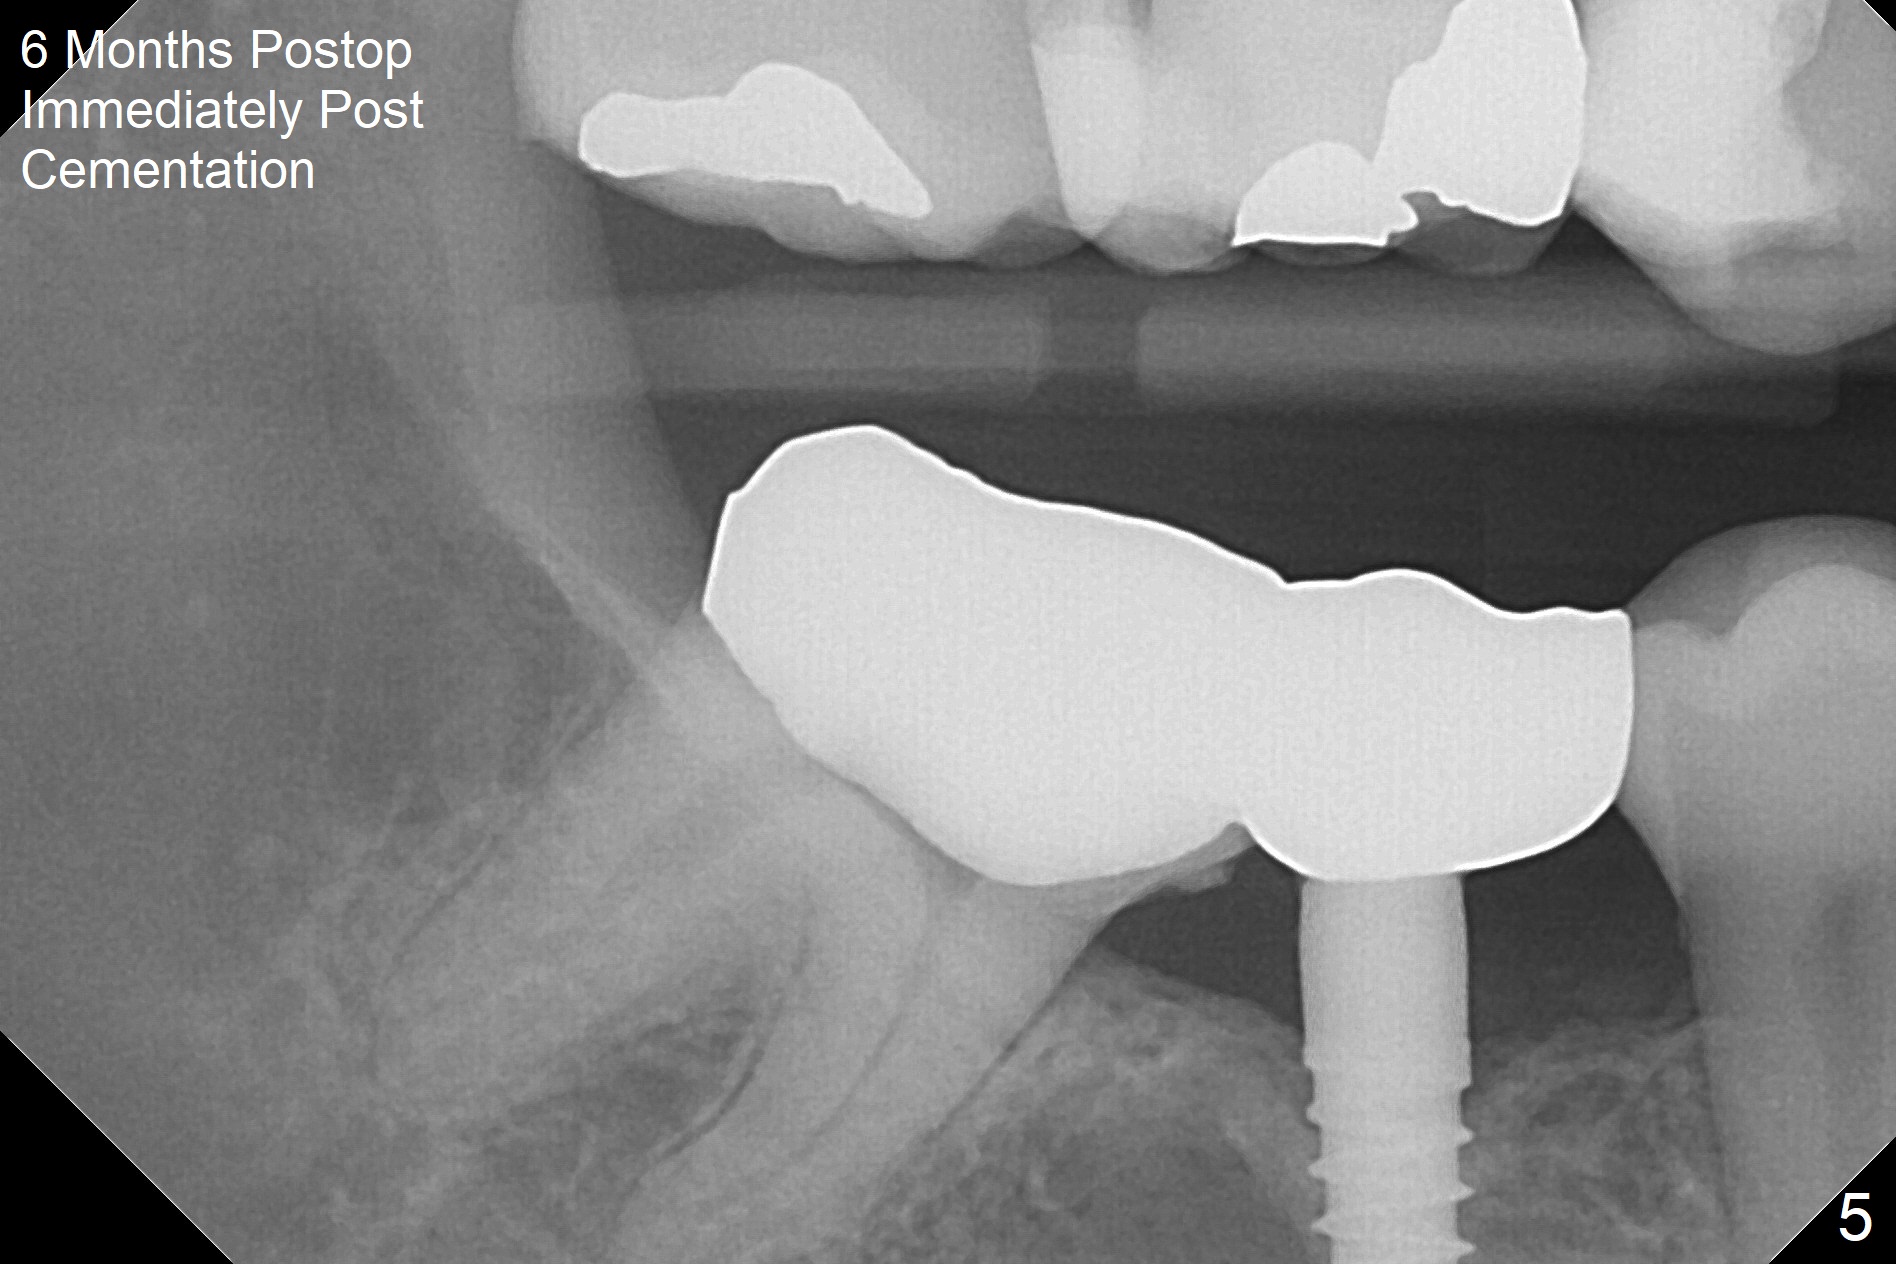

When a 1.2x12 mm drill is placed at #30, it passes the bone cavitation (Fig.1 red dashed line (low density)) twice for two-pointed fixation. So does the 3x12(2) mm 1-piece implant (Fig.2,3). The mesial margin of the tooth #31 is further reduced prior to suturing and periodontal dressing. Impression is taken 5 months postop (Fig.4). Residual cement mesial to the crown at #31 is later removed (Fig.5). Since the crowns were made at #30 and 31 at the same time, there appears no food impaction in between (Fig.6, 5.5 months post cementation).